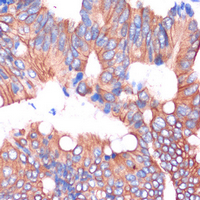

Immunohistochemical analysis of Cingulin staining in human colon cancer formalin fixed paraffin embedded tissue section. The section was pre-treated using heat mediated antigen retrieval with sodium citrate buffer (pH 6.0). The section was then incubated with the antibody at room temperature and detected using an HRP conjugated compact polymer system. DAB was used as the chromogen. The section was then counterstained with haematoxylin and mounted with DPX.